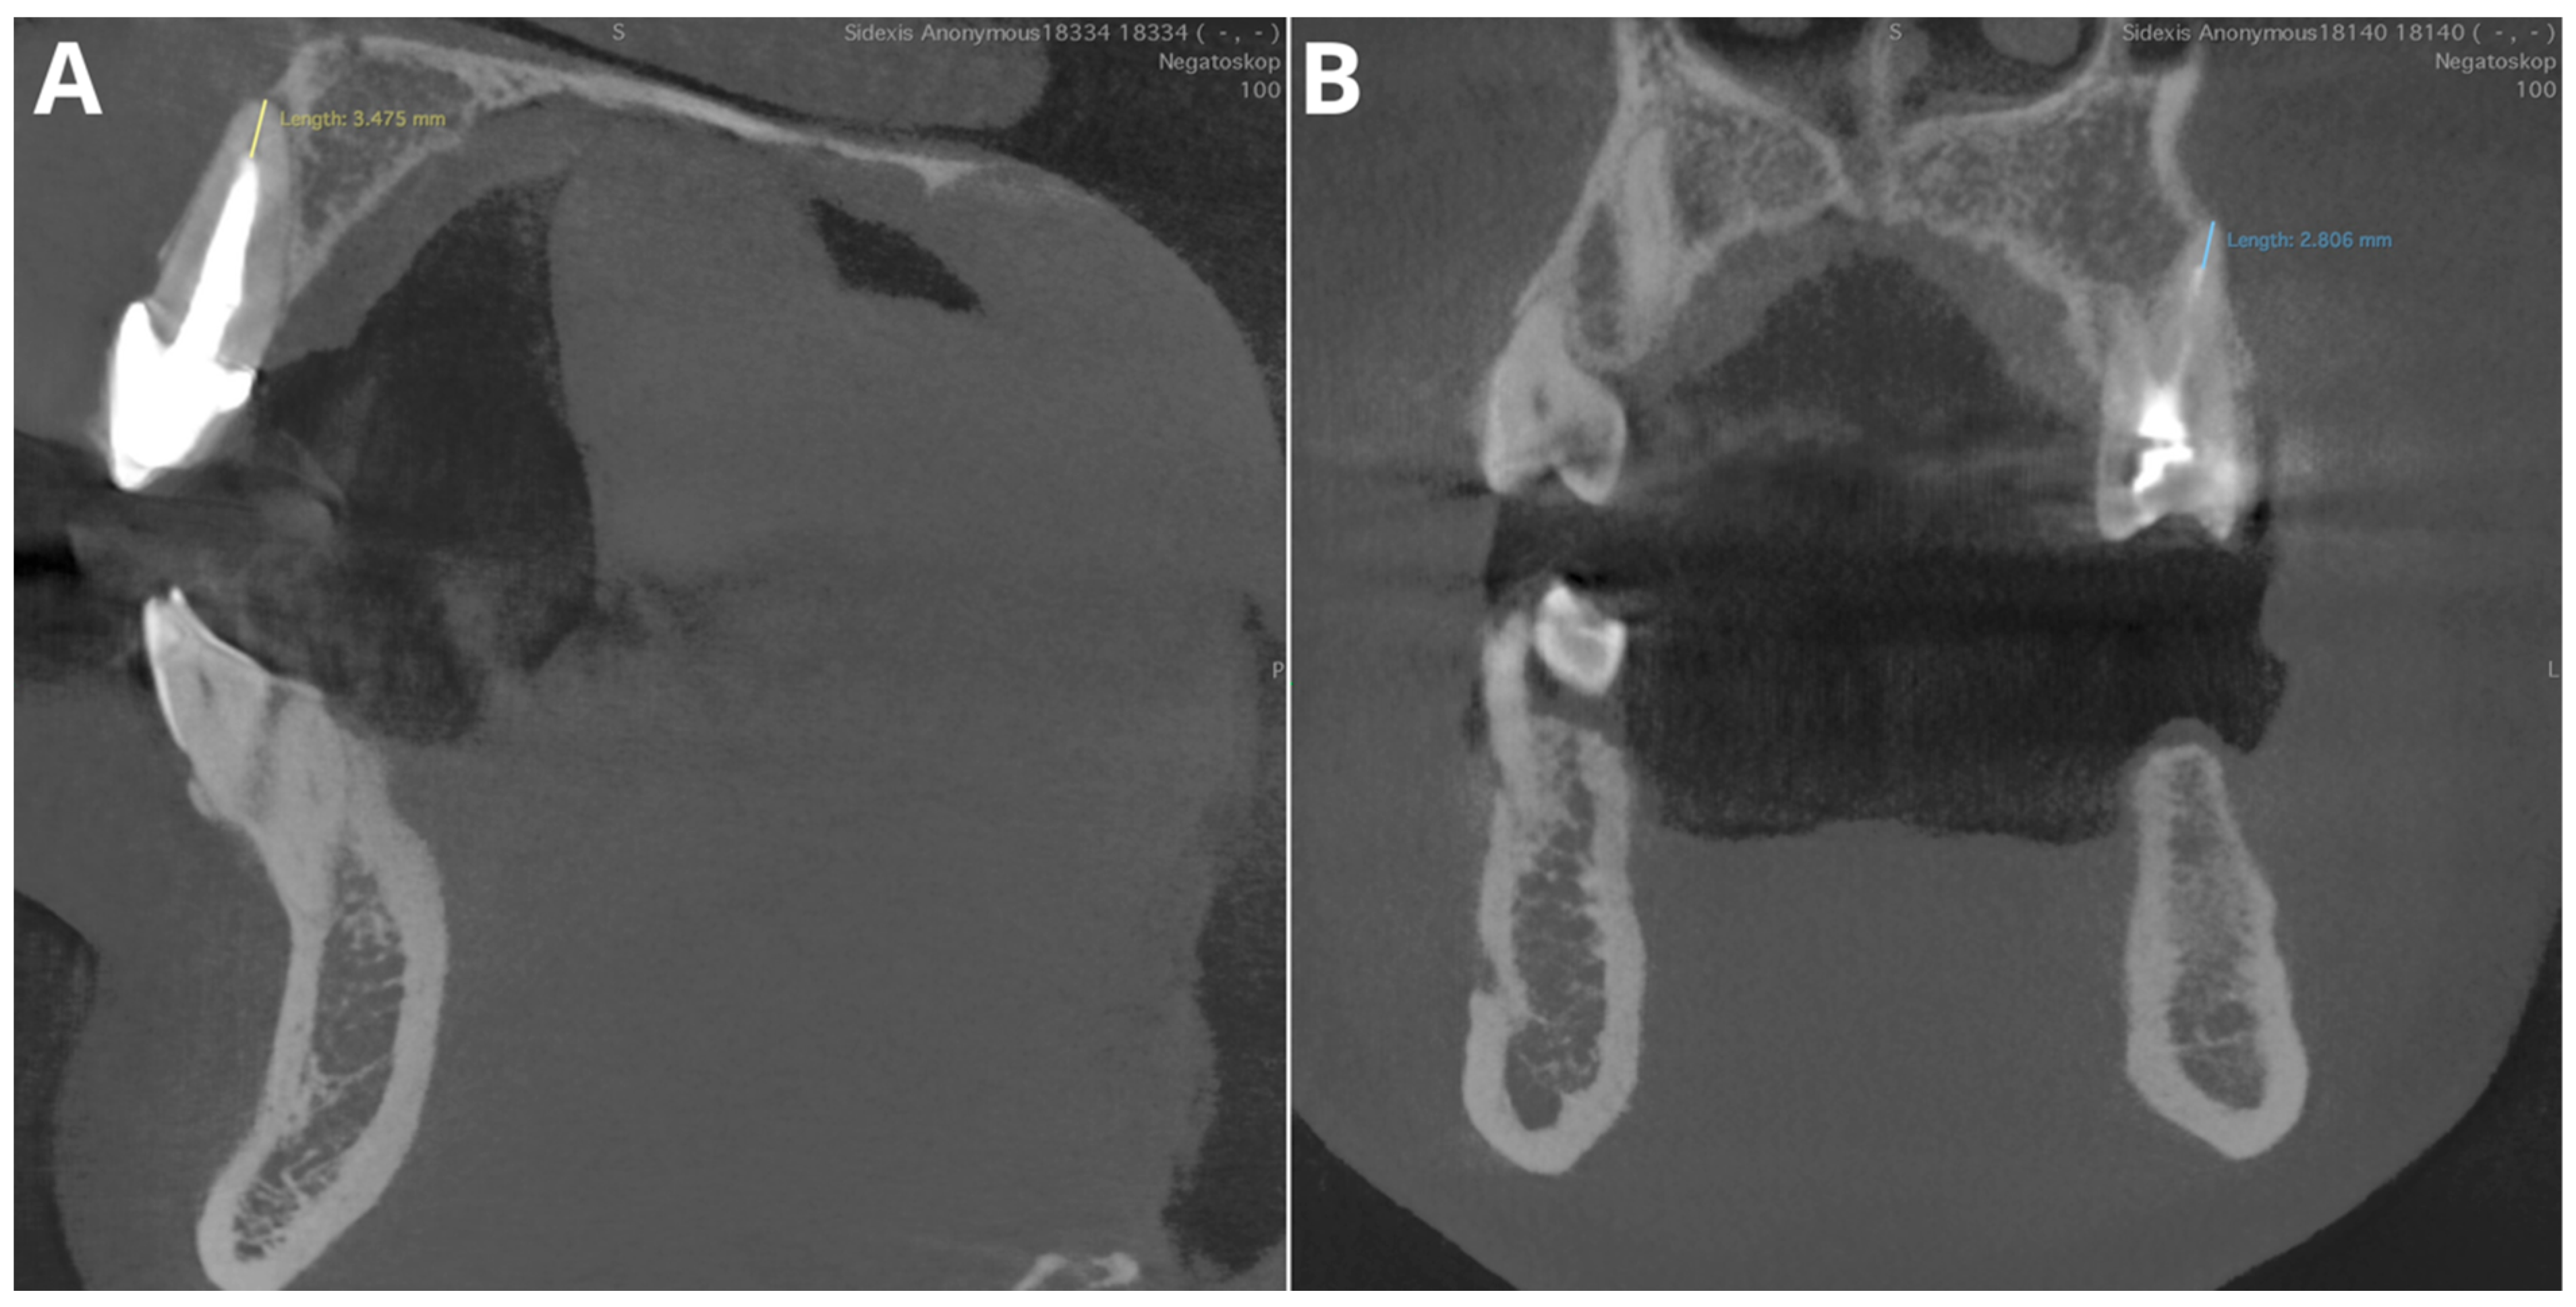

The performance for adequate density was notably high, with an accuracy of 95.5%, a precision of 97.2%, a recall of 97.2%, and an F1 score of 97.2%. Considering that this parameter relies on the subjective evaluation of the readers, we assume that the tested AI program exhibited perfect agreement with the readers’ assessments. Diagnosis revealed overfilling with high accuracy (95.5%), precision (86.7%), recall (100%), and F1 score (92.9%) on the CBCT images. An evaluation of the misdiagnoses revealed that all cases were very subtle (Figure 3). In contrast, Orhan et al. [26] reported a sensitivity of 66.7% for Diagnocat’s overfilling detection on panoramic images. These differences may stem both from the program’s algorithms’ improvements over time and from the different imaging modalities. Moreover, Diagnocat showed exceptional diagnostic accuracy in short-term assessments, with close to 100% accuracy. Figure 4 presents two of the false-negative diagnoses. The detection of voids by the AI program achieved lower performance than other parameters in our study, with 88.6% accuracy, 88.9% precision, 66.7% recall, and 76.2% F1 score. However, Orhan et al. reported a much lower sensitivity of 23.3% for void detection on panoramic images [26]. This discrepancy could be attributed to the 3D imaging provided by CBCT compared to the 2D panoramic images used in Orhan’s study. Our study revealed high accuracy and precision for diagnosing short fillings (95.5% and 100%, respectively), along with a recall of 86.7% and an F1 score of 92.9%. However, Orhan et al. reported a lower sensitivity of 70% [26].

In general, our results showed excellent diagnostic accuracy for Diagnocat in endodontic treatment evaluation. A detailed investigation during the preparation of figures revealed only one false positive diagnosis among all the evaluated features and teeth. A false positive diagnosis was made in the voids in the filling assessment (shown in Figure 5A). This finding aligns with the findings of other studies showing high specificity in diagnosing this condition, although with slightly lower sensitivity metrics [26,27,29,30,31]. These metrics demonstrate the “conservativeness” of the tested AI program, where at the cost of false negatives, there is no excessive number of false positives. The integration of such AI programs in endodontic diagnostics, particularly with CBCT imaging, presents several clinical advantages. It not only improves diagnostic accuracy but also standardizes the assessment process, thereby minimizing inter- and intraobserver variability. This is particularly beneficial in high-volume practices where consistent and rapid diagnostic evaluations are crucial.

Figure 5. Misdiagnoses in voids in filling feature assessment. (A)—tooth 35—false positive; (B)—tooth 21—false negative; (C)—tooth 34—false negative; (D)—tooth 13—false negative.